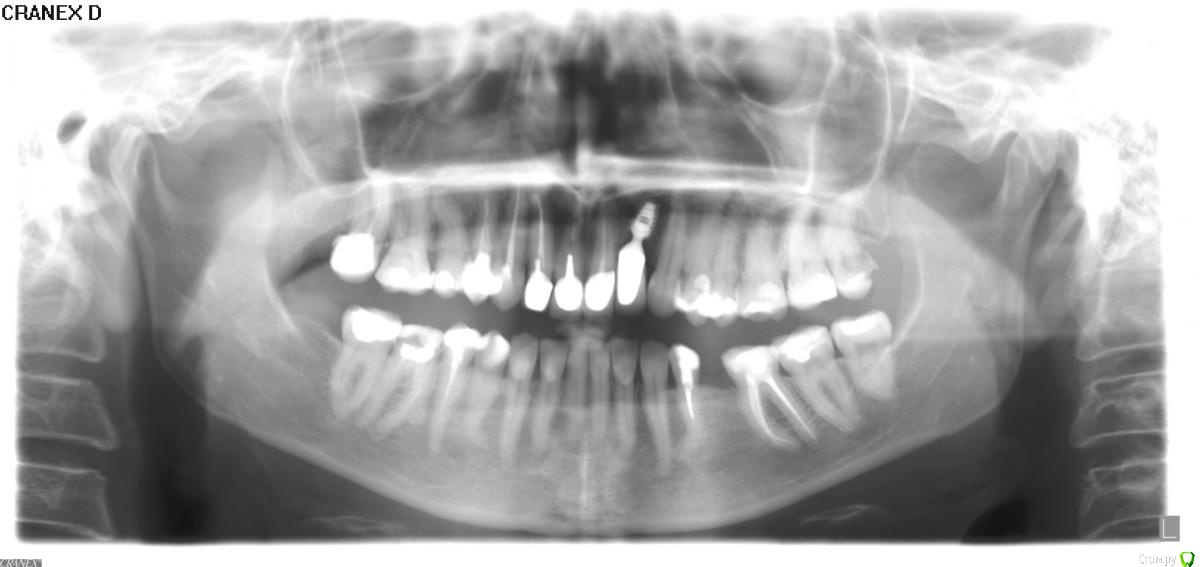

Ирина Анатольевна Опубликовано 30 ноября, 2014 Поделиться Опубликовано 30 ноября, 2014 Здравствуйте,уважаемые доктора. Год назад мне был установлен имплант Байкон. Как сказал ортопед, который потом занимался протезированием, установлен он очень глубоко, поэтому эстетика получилась "не очень", зуб какой-то слишком длинный. Утешает то, что даже при самой широкой улыбке десну у меня не видно, поэтому что либо из-за этого переделывать не хочется, да и все это очень сложно, как я понимаю. Беспокоит меня другое - нормально ли что стоит он не только глубоко, но еще и как-то очень криво, и вообще все ли с ним в порядке, потому что при артикуляции я постоянно чувствую десну вокруг импланта? Может его вообще лучше удалить? Ссылка на комментарий